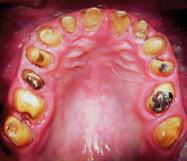

El objetivo de este artículo es presentar un paciente masculino pediátrico de 2 años 11 meses de edad que muestra la ocurrencia clínica de odontoma compuesto con características histológicas de fibrodentinoma ameloblástico, en la región anterior del maxilar entre los órganos dentarios del canino superior izquierdo al segundo molar superior del mismo lado (6365), sitio de presencia informado poco común. El paciente fue atendido de forma interdisciplinaria, a los 6 meses de postoperado el paciente no presentó recidiva o algún síntoma.

Paciente masculino de 2 años 11 meses de edad., que se presentó a la consulta privada, la tía lo lleva a la consulta por falta de erupción del

canino superior izquierdo, a la exploración clínica se observó un aumento de volumen de campos profundos, blando y depresible, a nivel del canino superior izquierdo que se extendía hasta el fondo de saco y mucosa interna labial, así como, ausencia de la pieza dental sin antecedentes de extracción, No había dolor, sangrado ni secreción, asociados con el aumento de volumen.

El examen clínico reveló un aumento de volumen en la zona de órganos dentarios 63-65 que se extendía al seno maxilar, con desplazamiento de cortical vestibular, sin perforación ni cambio de color en la mucosa, de estructura uniforme bien delimitada. (Figura 1). En el examen radiográfico se observó la expansión de la cortical, con la presencia de múltiples dentículos. Desplazamiento del órgano

dentario 63 hacia el seno maxilar (Figura 2).

Bajo anestesia general, se realizó la escisión quirúrgica de la lesión, junto con la extracción del canino superior izquierdo de la primera dentición impactado. El tumor era de color marrón y medía aproximadamente 50 × 13 mm.

La muestra se envió para análisis histopatológico (Figura 3).